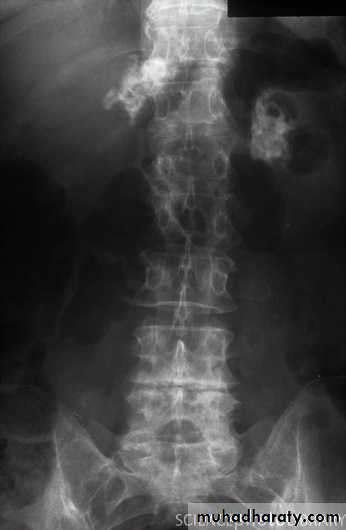

Tuberculosis cause adrenal calcification seen on plain abdominal X-ray